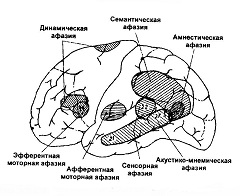

Согласно классификации А. Р. Лурии можно выделить различные формы афазии:

- Эфферентная моторная афазия (иначе афазия Брока – по имени врача, описавшего симптомы заболевания) возникает на фоне поражения нижних отделов премоторной коры левого полушария мозга. Моторную афазию характеризует телеграфный стиль высказываний (распад грамматики), а также трудности в переключении с одного слова или словосочетания на другое. Еще одной характерной особенностью проявления моторной афазии являются нарушения письма и чтения;

- Для проявления динамической афазии характерна невозможность построения внутренней программы высказывания (распад внутренней речи). Это расстройство вызывает поражение префронтальной области левого полушария;

- В основе сенсорной афазии (иначе афазия Вернике) лежит поражение коркового отдела слухового анализатора. При сенсорной афазии больной теряет способность интерпретировать услышанную речь;

- К развитию афферентной моторной афазии приводит поражение теменной и задне-центральной областей коры. При этом больные афазией испытывают затруднения из-за невозможности различать близкие по артикуляции звуки по причине неправильно подобранной артикуляционные позы, что приводит к смешиванию артикулем внутри группы;

- Оптико-мнестическую афазию характеризует слабость зрительных образов слов и нарушение зрительной памяти. Больные афазией испытывают трудность в назывании слов;

- Акустико-мнестическую афазию вызывает сужение объема слухоречевой памяти и нарушение объема удержания слухоречевой информации;

- Амнестическую афазию вызывают поражения теменно-височной области, а основная трудность состоит в назывании знакомых предметов;

- Семантическую афазию характеризуют дефекты симультанного синтеза и анализа речи, а также нарушение понимания сложных логико-грамматических конструкций, которые описывают пространственные отношения.